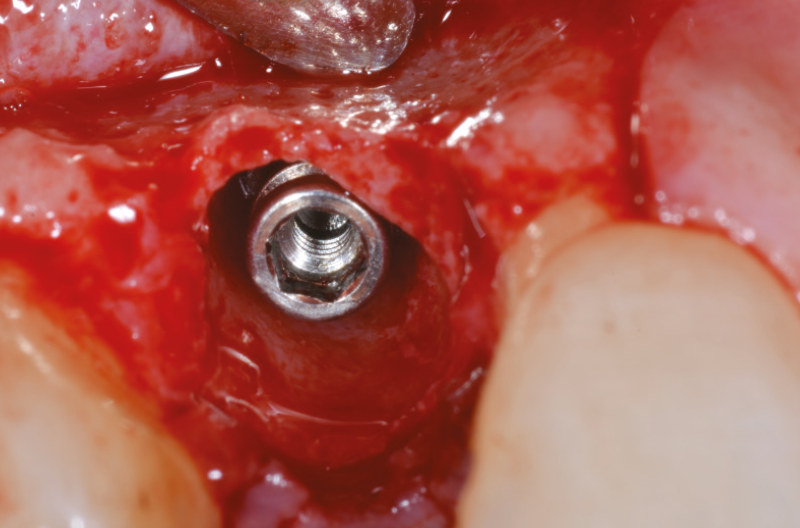

A questo punto inseriamo un impianto Leone XCN® Max Stability da 3,75 mm di diametro per 14 mm di lunghezza con contrangolo da implantologia (Fig. 18) e ne completiamo il posizionamento con un cricchetto manuale, fino a posizionare l’impianto 2 mm sotto la cresta ossea (Figg. 19-21).

Fig. 18 – Inserimento di un impianto XCN® Max Stability D 3,75 mm

Fig. 19 – Inserimento di un impianto XCN® Max Stability D 3,75 mm

Fig. 20 – Impianto inserito 2 mm sotto la cresta ossea

Fig. 21 – Impianto inserito 2 mm sotto la cresta ossea